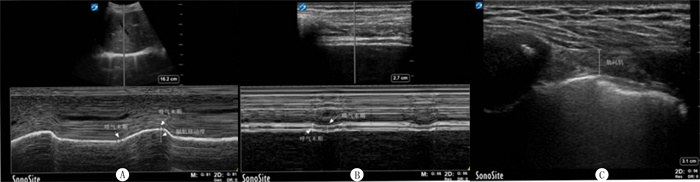

1.2 研究方法采用索诺声公司生产的X-PORTE超声检测仪进行数据采集。对符合条件的病人,在暂停呼吸机30 min后,利用3.5 MHz凸阵探头测量膈肌移动度(DE)、膈肌增厚分数(DTF)以及肋间肌增厚分数(TFic)。①DE的测量:床头抬高30°,将探头置于右腋前线与肋缘交界处,经肝脏透声窗,指向膈肌中后1/3处,采用M型超声模式,垂直于膈肌放置采样线,测量呼气末与吸气末膈肌距离基线的平均值。②DTF测量:床头抬高30°,使用10 MHz线阵探头在右腋中线第8~10肋间隙观察膈肌,测量吸气末与呼气末膈肌厚度,取3个周期的平均值,经公式DTF=(吸气末膈肌厚度-呼气末膈肌厚度)/呼气末膈肌厚度×100%,计算DTF。③TFic测量:在右侧胸骨旁的4、5肋间,测量吸气末与呼气末肋间肌厚度,计算3个周期的平均值,经公式TFic=(吸气末肋间肌厚度-呼气末肋间肌厚度)/呼气末肋间肌厚度×100%,得出TFic。膈肌和右侧肋间肌超声测量见图 1。

| A:DE超声测量;B:DTF超声测量;C:右侧肋间肌超声测量。 图 1 膈肌和右侧肋间肌超声测量 |